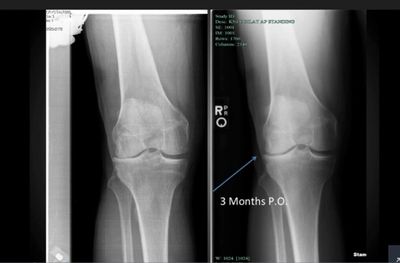

At Regenerative Biologics Institute (RBI), Dr. Fritz met with clinical director and stem cell scientist Jason Griffeth, MS. After looking at a series of x-rays that showed Dr. Fritz was suffering from arthritic degeneration of the cartilage in both knees, RBI’s medical team recommended a combination of TruGenta™ Injection Therapy and Peptide Therapy.

In the phase I safety trial, a single injection of adipose tissue derived stem cells into the knee patients was safe and well tolerated.

The stem cell treatment also showed durable and clinically meaningful pain relief in patients with knee osteoarthritis.

Examination of knee joint structure by MRI showed a statistically significant improvement in lateral tibial cartilage volume for patients treated with the stem cells. This result compared to a worsening in volume in placebo patients.